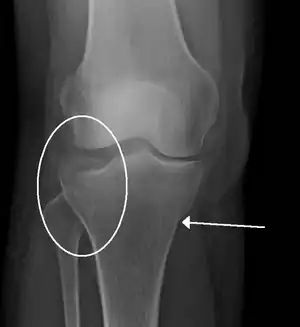

Subtle tibial plateau fracture on an AP X ray of the knee